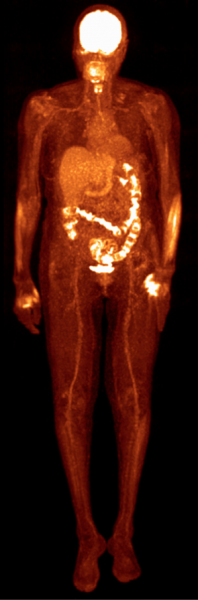

December 13, 2013 — Philips unveiled the Vereos PET/CT fully digital positron emission tomography/computed tomography (PET/CT) imaging system at the Radiological Society of North America Annual Meeting (RSNA 2013) in Chicago.

Based on Philips’ proprietary digital photon counting technology, the Vereos PET/CT is the first PET/CT system in the industry to use digital silicon photomultiplier detectors instead of traditional analog detectors, resulting in a step change in performance that approximately doubles sensitivity gain, volumetric resolution and quantitative accuracy compared to analog systems. These radical improvements can ultimately be translated into high image quality, increased diagnostic confidence, improved treatment planning and faster workflows.

In a recent survey, nine out of ten referring physicians preferred Vereos digital PET/CT images over images taken with an analog system. Philips has received 510(k) clearance from the U.S. Food and Drug Administration (FDA) to market its digital PET/CT system in the United States.